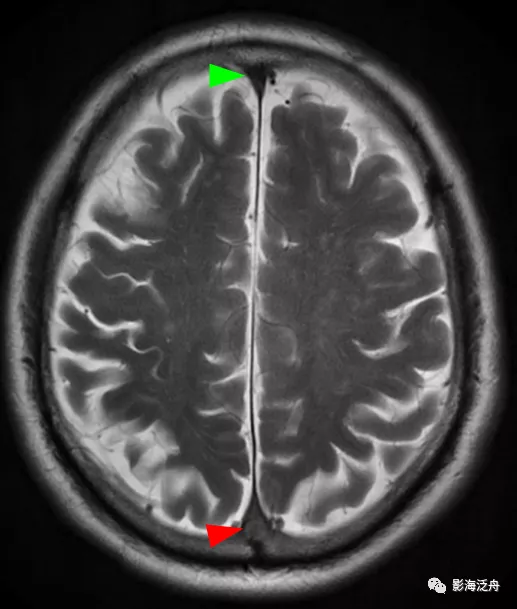

病例三:患者男,67歲,頭暈伴頭痛1周,既往有腦梗死病史,血壓145/95mmHg,神經系統查體無殊。

病例三:靜脈竇血栓。正常情況下,上矢狀竇在SE序列(T1WI)和FSE(T2WI)序列上均呈流空低訊號(綠箭頭),本例中上矢狀竇呈等高訊號(紅箭頭),結合患者頭痛病史,應考慮上矢狀竇血栓。